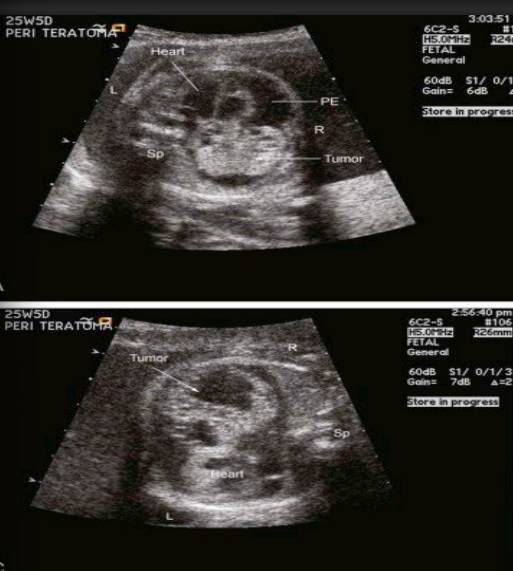

Teratoma, its a what tumor attached to where?

where is it found?

A single tumor attached to the base •

found in the pericardial reflection at the junction of SVC, RA, AsAo

Teratoma

what chamber does it impinges on? and they cause what of the what (name 3 things)

Impinges on the right atrium and they cause compression of the SVC, great arteries and cardiac chambers

Teratoma, always accompanies by what? what are with the tumor

Always accompanies by pericardial effusion

Multicystic areas within the tumor

what are the hemodynamic consequences in utero, what do they cause and what are they associated with?

They have hemodynamic consequences in utero and grow rapidly

May cause tamponade and are associated with hydrops up to ~80%

(Intervention in utero is necessary)